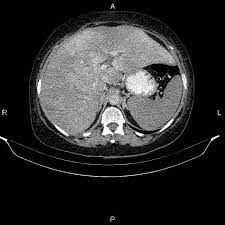

Chiasmata -mə-tə or chiasmas also chiasms 1. Esophageal varices are extremely dilated sub-mucosal veins in the lower third of the esophagus. Located in metro Denver northern Colorado and western Nebraska serving all of the Front Range our team consists of board-certified and fellowship-trained interventional radiologists. This results in hepatic congestion similar to Budd-Chiari syndrome and post-sinusoidal portal hypertension. The patients condition should be monitored throughout the procedure. They are most often a consequence of portal hypertension commonly due to cirrhosis. Toxic injury to liver sinusoids causes sloughing of endothelial cells that embolize to hepatic venules and cause eventual fibrosis of the venules. Coin in the Esophagus. There is no clear consensus regarding the number of occluded veins some authors claim that there should be at least one occluded hepatic vein 7 others state that there are no significant.

Carcinoma of the Colon. Budd-Chiari syndrome a blockage in one or more veins that carry blood from the liver back to the heart. And coumarin skin necrosis adrenal gland hemorrhage and infarction. Toxic injury to liver sinusoids causes sloughing of endothelial cells that embolize to hepatic venules and cause eventual fibrosis of the venules. Chiari malformation CM is a structural defect in the cerebellum characterized by a downward displacement of one or both cerebellar tonsils through the foramen magnum the opening at the base of the skull. Embolism and thrombosis of. La présence dune ou plusieurs affections prothrombotiques est fréquente La prise en charge repose sur un traitement anticoagulant précoce le traitement de l.